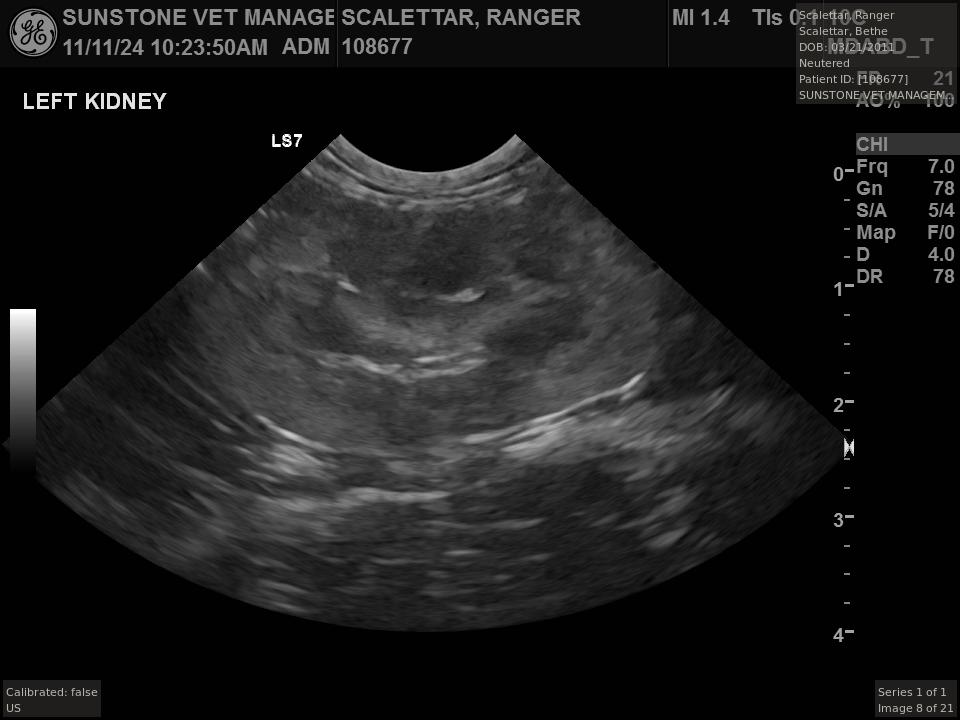

The veterinarian generated a series of images showing different organs and substructures by

changing the position and orientation of the ultrasound transducer. The images were collected

in a defined order, which is repeated from patient to patient, ensuring that nothing is missed. In

Ranger's case, the sonographer collected about twenty images during an examination that

lasted about fifteen minutes.

The sonographer stated that Ranger's ultrasound images were largely normal for an older cat. In particular, they show changes in the kidneys that are commonly noted in geriatric cats and that reflect a risk for the development of chronic kidney disease. However, the images did not show any significant abnormalities in Ranger's stomach, intestines, and associated lymph nodes. Nonetheless, the results did not rule out recurrence of Ranger's small cell lymphoma.